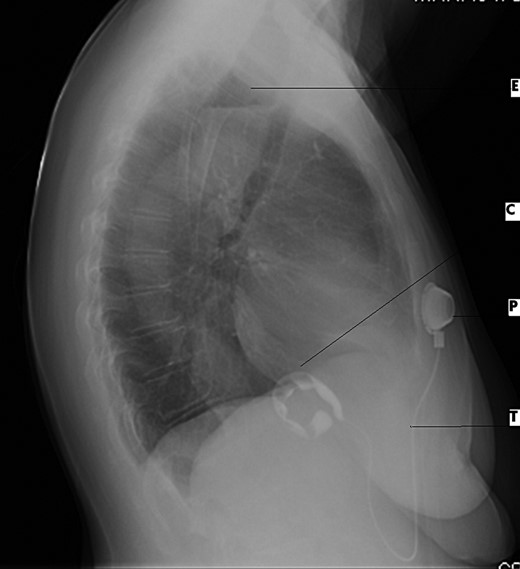

Electrocardiogram was remarkable for Q waves in leads I, aVL and V6. Chest X-ray (CXR) demonstrated a marked esophageal distention with an air fluid level (Figs 1 and 2).

Lateral CXR view demonstrates dilated esophagus and fluid air level (E), contrast medium-filled inflatable inner cuff (C), connecting silicone tube (T) and subcutaneous sutured radiopaque access port (P).